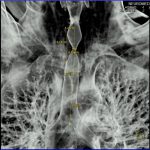

Examinare de rutină cerebrală, nativ și cu substanță de contrast (SDC) pentru diagnosticul:

- Accidentelor vasculare cerebrale ischemice sau hemoragice

- Tumorilor cerebrale